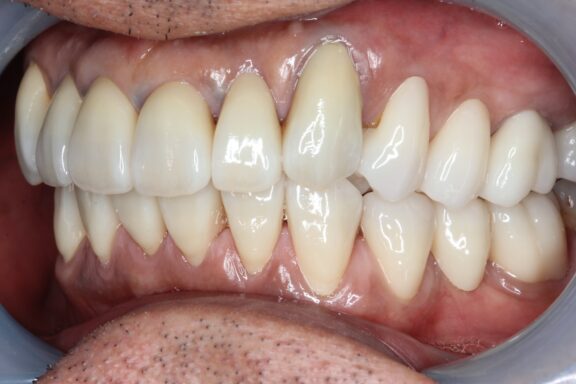

完成がこちらになります。

必要箇所には顕微鏡(マイクロスコープ)にて根管治療を行い、先月、全部の治療が完成しました。

術前、術後で比較すると、とても口腔内が明るくなり、正面から見てもとても若々しく感じます

今回は約1年ほどかけながら順番にゆっくり焦らずしっかりと治療を行っていきました。